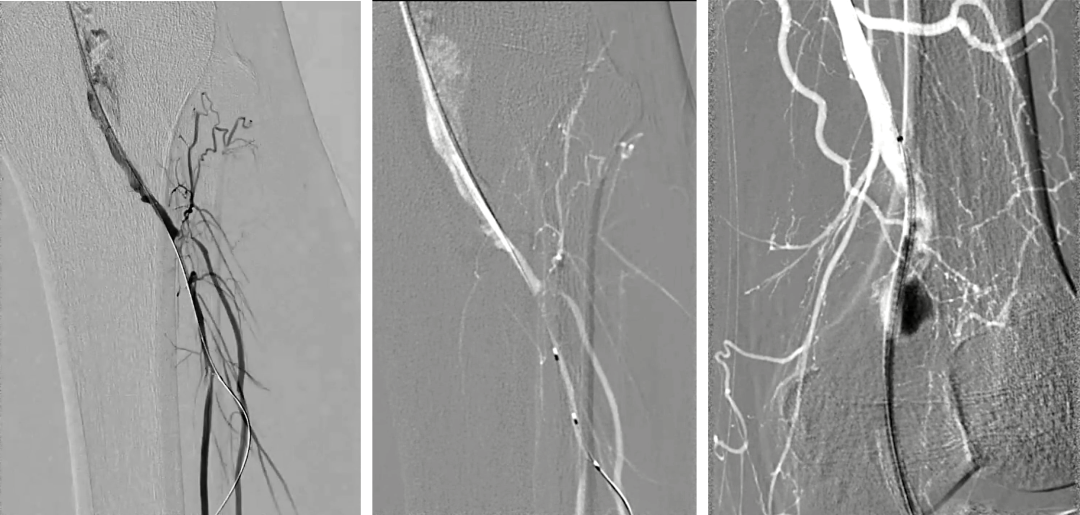

8.造影见动脉瘤消失、支架通畅、腘动脉远端狭窄和造影剂滞留;自近端将导丝置入腓动脉,3mm×60mm球囊扩张;造影见腓动脉形态良好,无造影剂滞留,见胫前动脉开口狭窄;

9. 入胫前动脉,3mm×60mm球囊扩张;由于脉管炎血管扩张后发生痉挛,予罂粟碱10mg后,胫前动脉和腓动脉近中段血流通畅,但仍存少量痉挛后狭窄,远端流出道通畅;